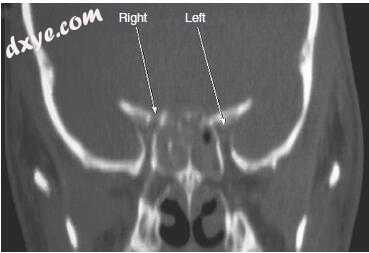

19.jpg

图-19. 冠状面计算机断层扫描显示视神经管的双侧骨折。